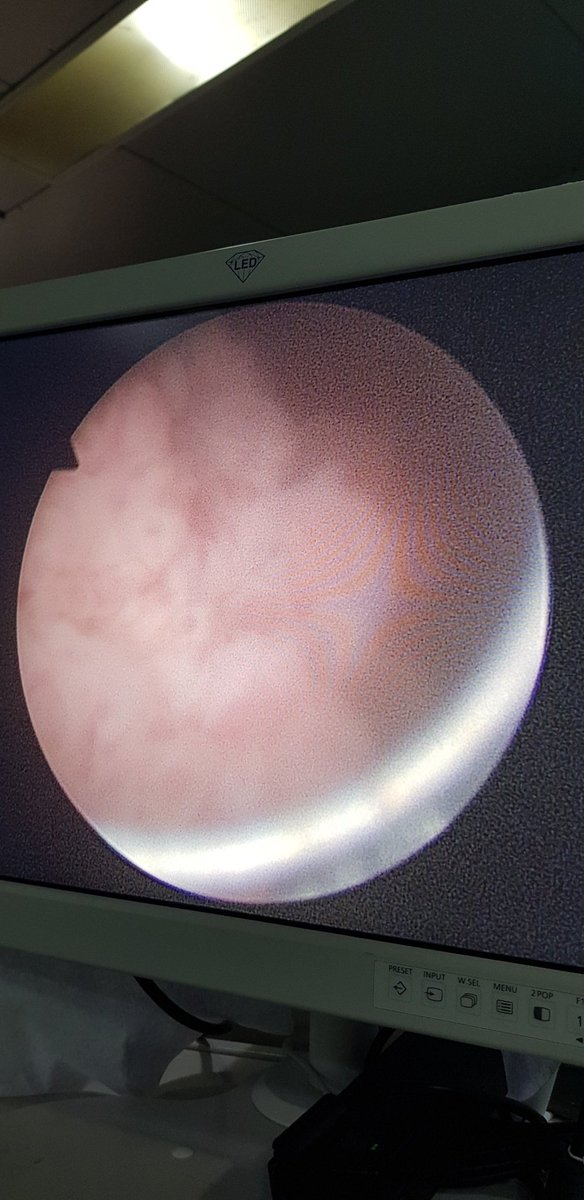

Cerita Malam Tentang Kanker Kandung Kemih

Mungkin sdh ratusan kali pasien datang k praktek saya dgn keluhan kencing bercampur darah. Terkadang ada gumpalan hitam. Yg khas dr keluhan mereka adalah mayoritas tdk mengeluh nyeri kecuali bila gumpalan darah menyumbat

Nyeri baru tjd kalau aliran kencing terhambat. Keluhan kencing darah tsb bs berpekan2 hingga bulanan. Dugaan sy adalah mereka kena kanker kandung kemih. Dan itu terbukti dr hasil pemeriksaan usg atau ct scan abdomen. Selanjutnya y sy lakukan operasi.Ntar kpn2 sy cerita operasinya

Trus kenapa kok pasien kanker kandung kemih gak ngeluh nyeri atau ada benjolan d perut gitu. Y karena pertumbuhan tumor dari dinding dan masuk k dlm kandung kemih. Makanya tdk menyumbat aliran kencing & tdk bs diraba dr luar. Kecuali kalau udah stadium lanjut.